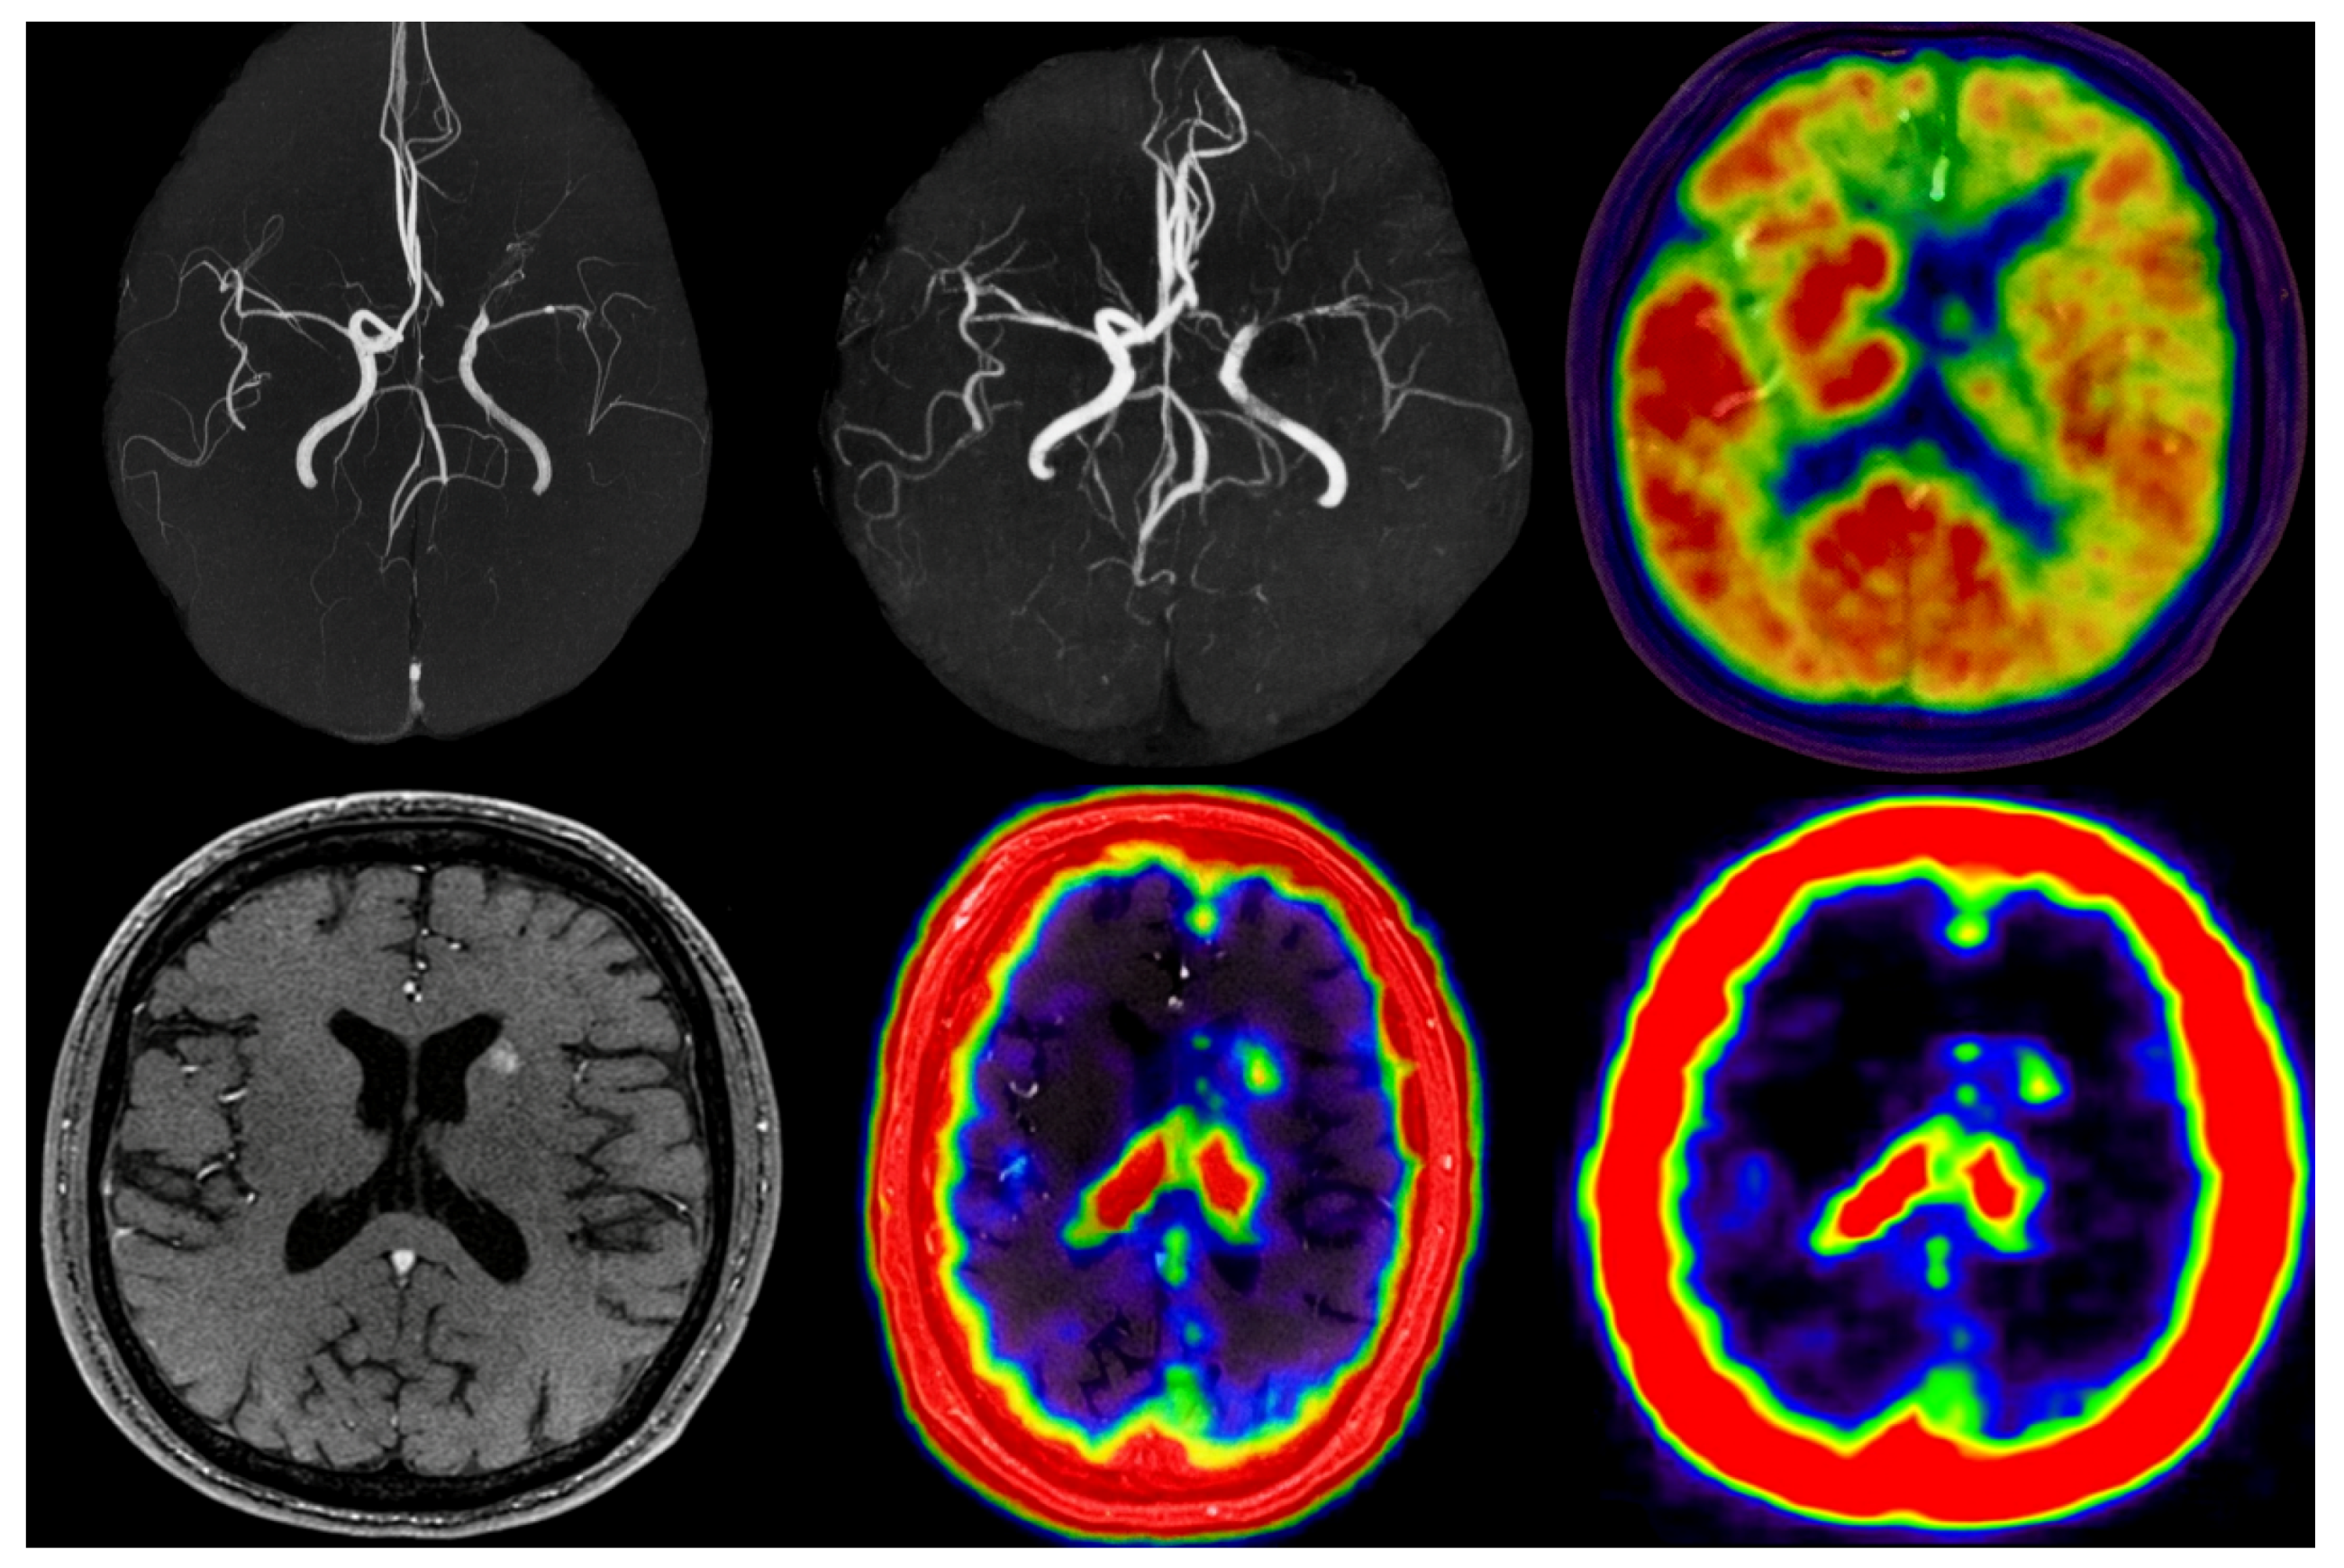

Figure 9. Clinical multimodal validation. Images are min–max normalized (MRA: [0, 1], PET: SUV units); scale bars indicate intensity ranges. Color in PET and fused MR–PET images represents tracer uptake (SUV) or perfusion intensity, ranging from low (blue) to high (red) values.